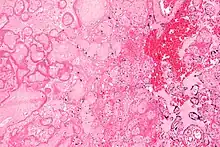

| Micrograph of a placental infarct (left of image), a cause of intrauterine hypoxia. H&E stain. | |